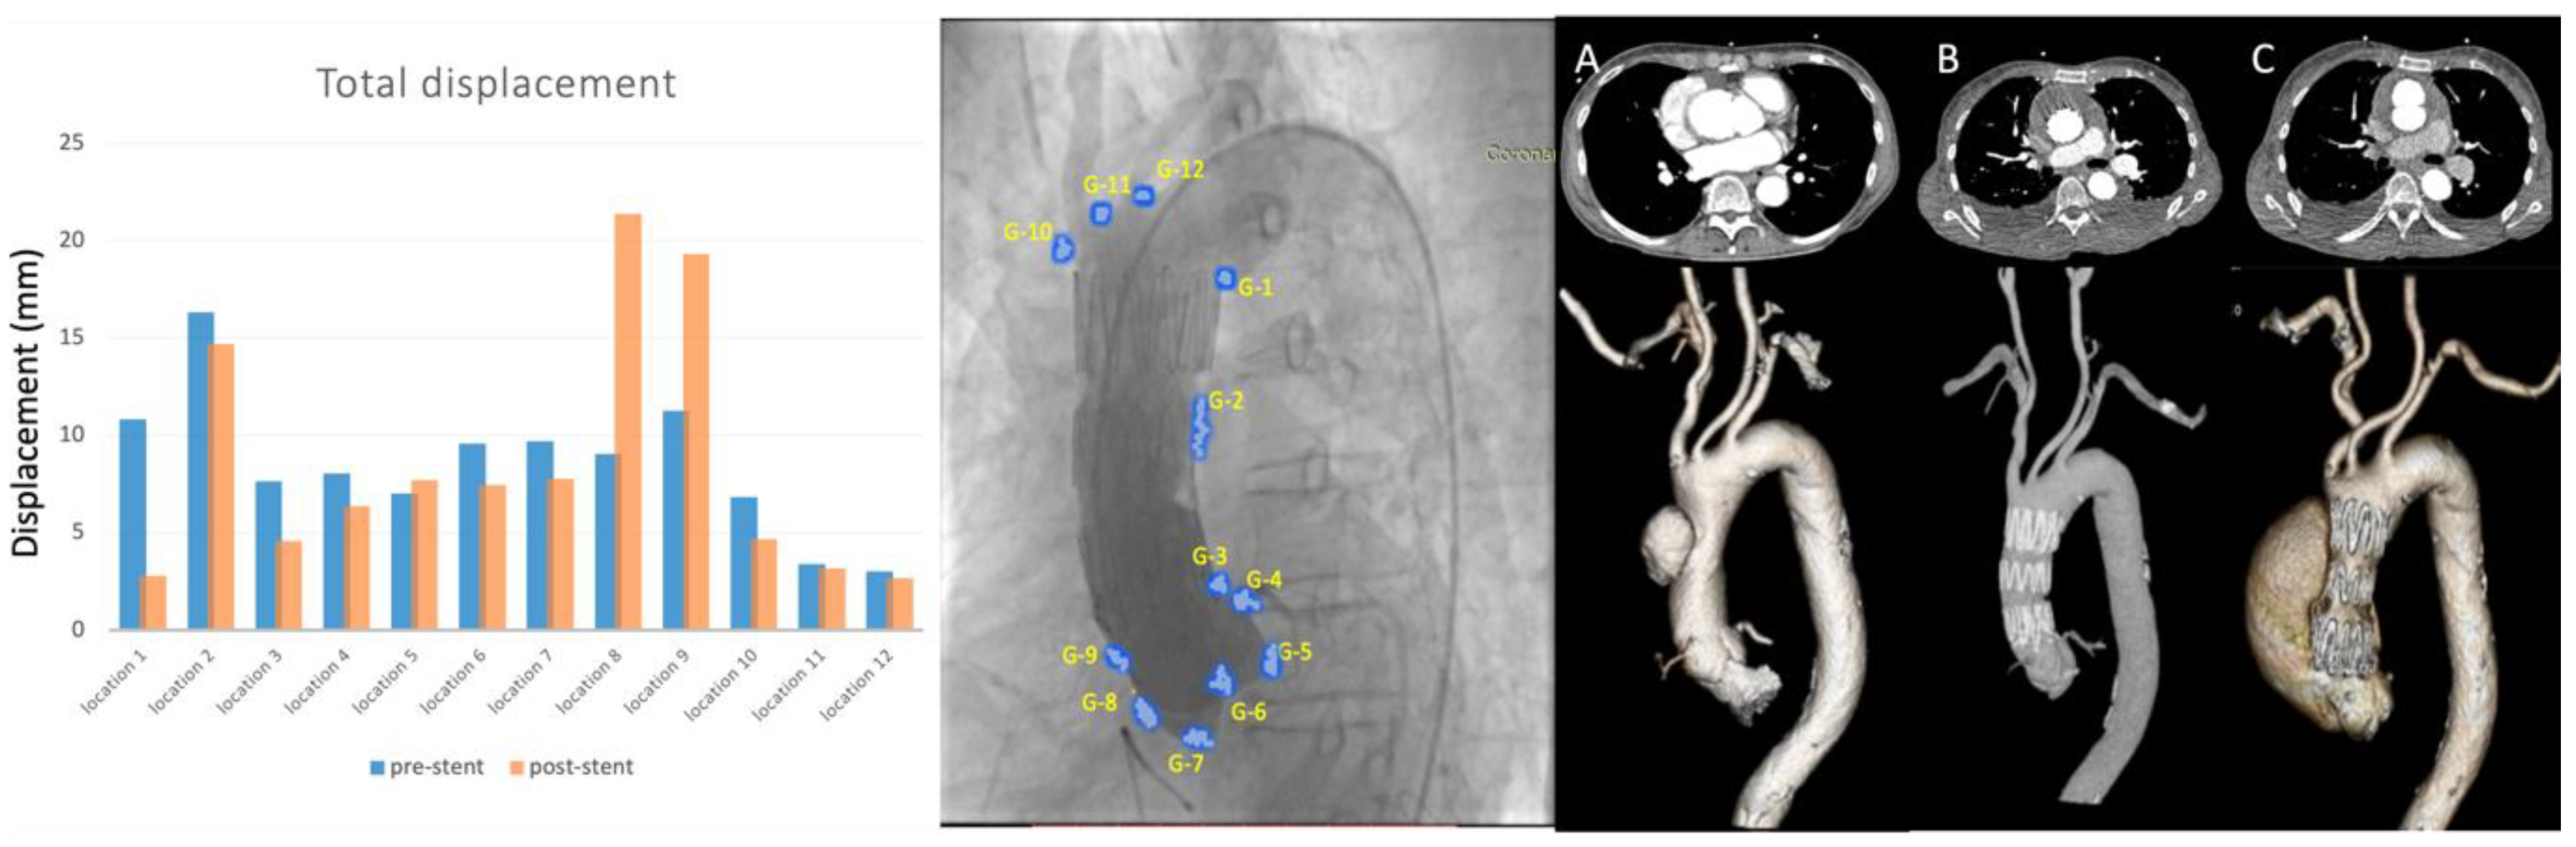

| Displacement (mm) | Group I—Stent Graft | Group II—Occluding Device | ||||

|---|---|---|---|---|---|---|

| Patient 1 | Patient 2 | Patient 3 | Patient 4 | Patient 5 | Patient 6 | |

| Pre-procedure | 6.84 | 8.51 | 6.78 | 5.59 | 3.23 | 13.3 |

| Post-procedure | 3.16 | 7.53 | 4.01 | 5.23 | 3.66 | 15.6 |

| Motion changed | −53.8% | −11.5% | −40.9% | −6.41% | +13.2% | +17.4% |